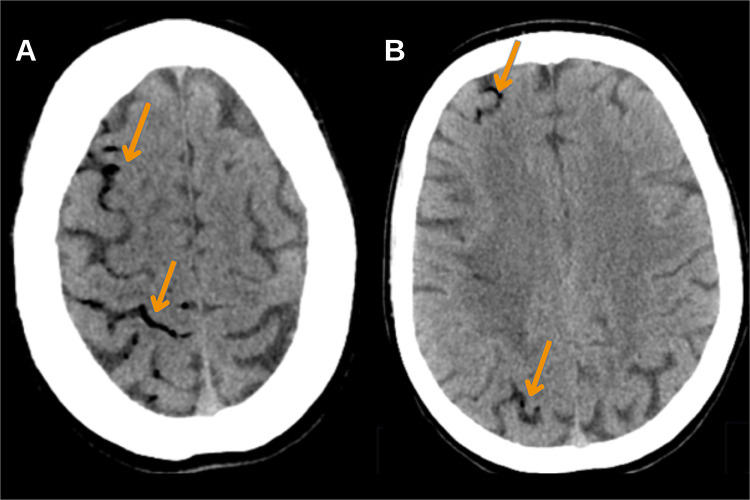

Case presentation: We present a rare case of cerebral infarction as a complication of retrograde cerebral venous air embolism following haemodialysis catheter removal in a young patient, with management leading to a favourable outcome. The diagnosis was confirmed based on clinical manifestations and neuroimaging findings, with air emboli identified in the subarachnoid space on the CT scan, followed by characteristic MRI changes defined for cerebral air embolism infarcts. Timely diagnosis allowed for the rapid initiation of hyperbaric oxygen therapy and the rehabilitation process, resulting in positive outcomes.

Conclusion: Timely neuroimaging-particularly CT within the first 2 hours-is critical for diagnosing CAEI. MRI findings, including cytotoxic and vasogenic oedema in a distal vascular distribution and leptomeningeal enhancement, further support diagnosis. Early identification and treatment initiation are essential for improving patient outcomes.